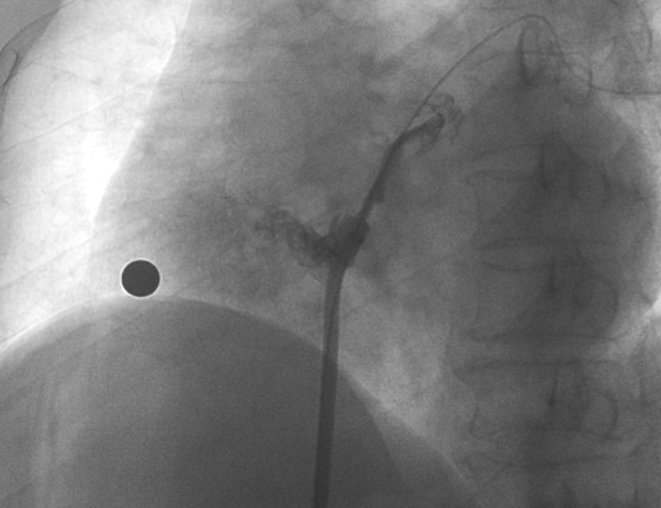

術(shù)中造影顯示患者為PFO且長(zhǎng)隧道型,目前市場(chǎng)上已商業(yè)化的PFO封堵器難以滿足該患者解剖結(jié)構(gòu)封堵需求。迪創(chuàng)醫(yī)療自主研發(fā)的OmniSeal PFO封堵器自適應(yīng)性雙盤貼合設(shè)計(jì)能廣泛適應(yīng)不同PFO隧道長(zhǎng)度的解剖結(jié)構(gòu)和形態(tài),其雙盤外包覆式阻流和隧道內(nèi)填充阻流相結(jié)合的雙重阻流設(shè)計(jì),可為此患者實(shí)現(xiàn)有效封堵。與此同時(shí),OmniSeal首創(chuàng)的完全可穿刺式設(shè)計(jì),也為此患者最大程度地保留了房間隔區(qū)域穿刺通道,以實(shí)現(xiàn)全兼容未來可能的左心系統(tǒng)二次介入術(shù)。術(shù)終造影和心臟超聲顯示封堵完全、效果良好。作為OmniSeal的首例臨床應(yīng)用,本次手術(shù)的順利完成和優(yōu)異效果充分體現(xiàn)了產(chǎn)品的設(shè)計(jì)創(chuàng)新優(yōu)勢(shì)。

造影顯示長(zhǎng)隧道型PFO